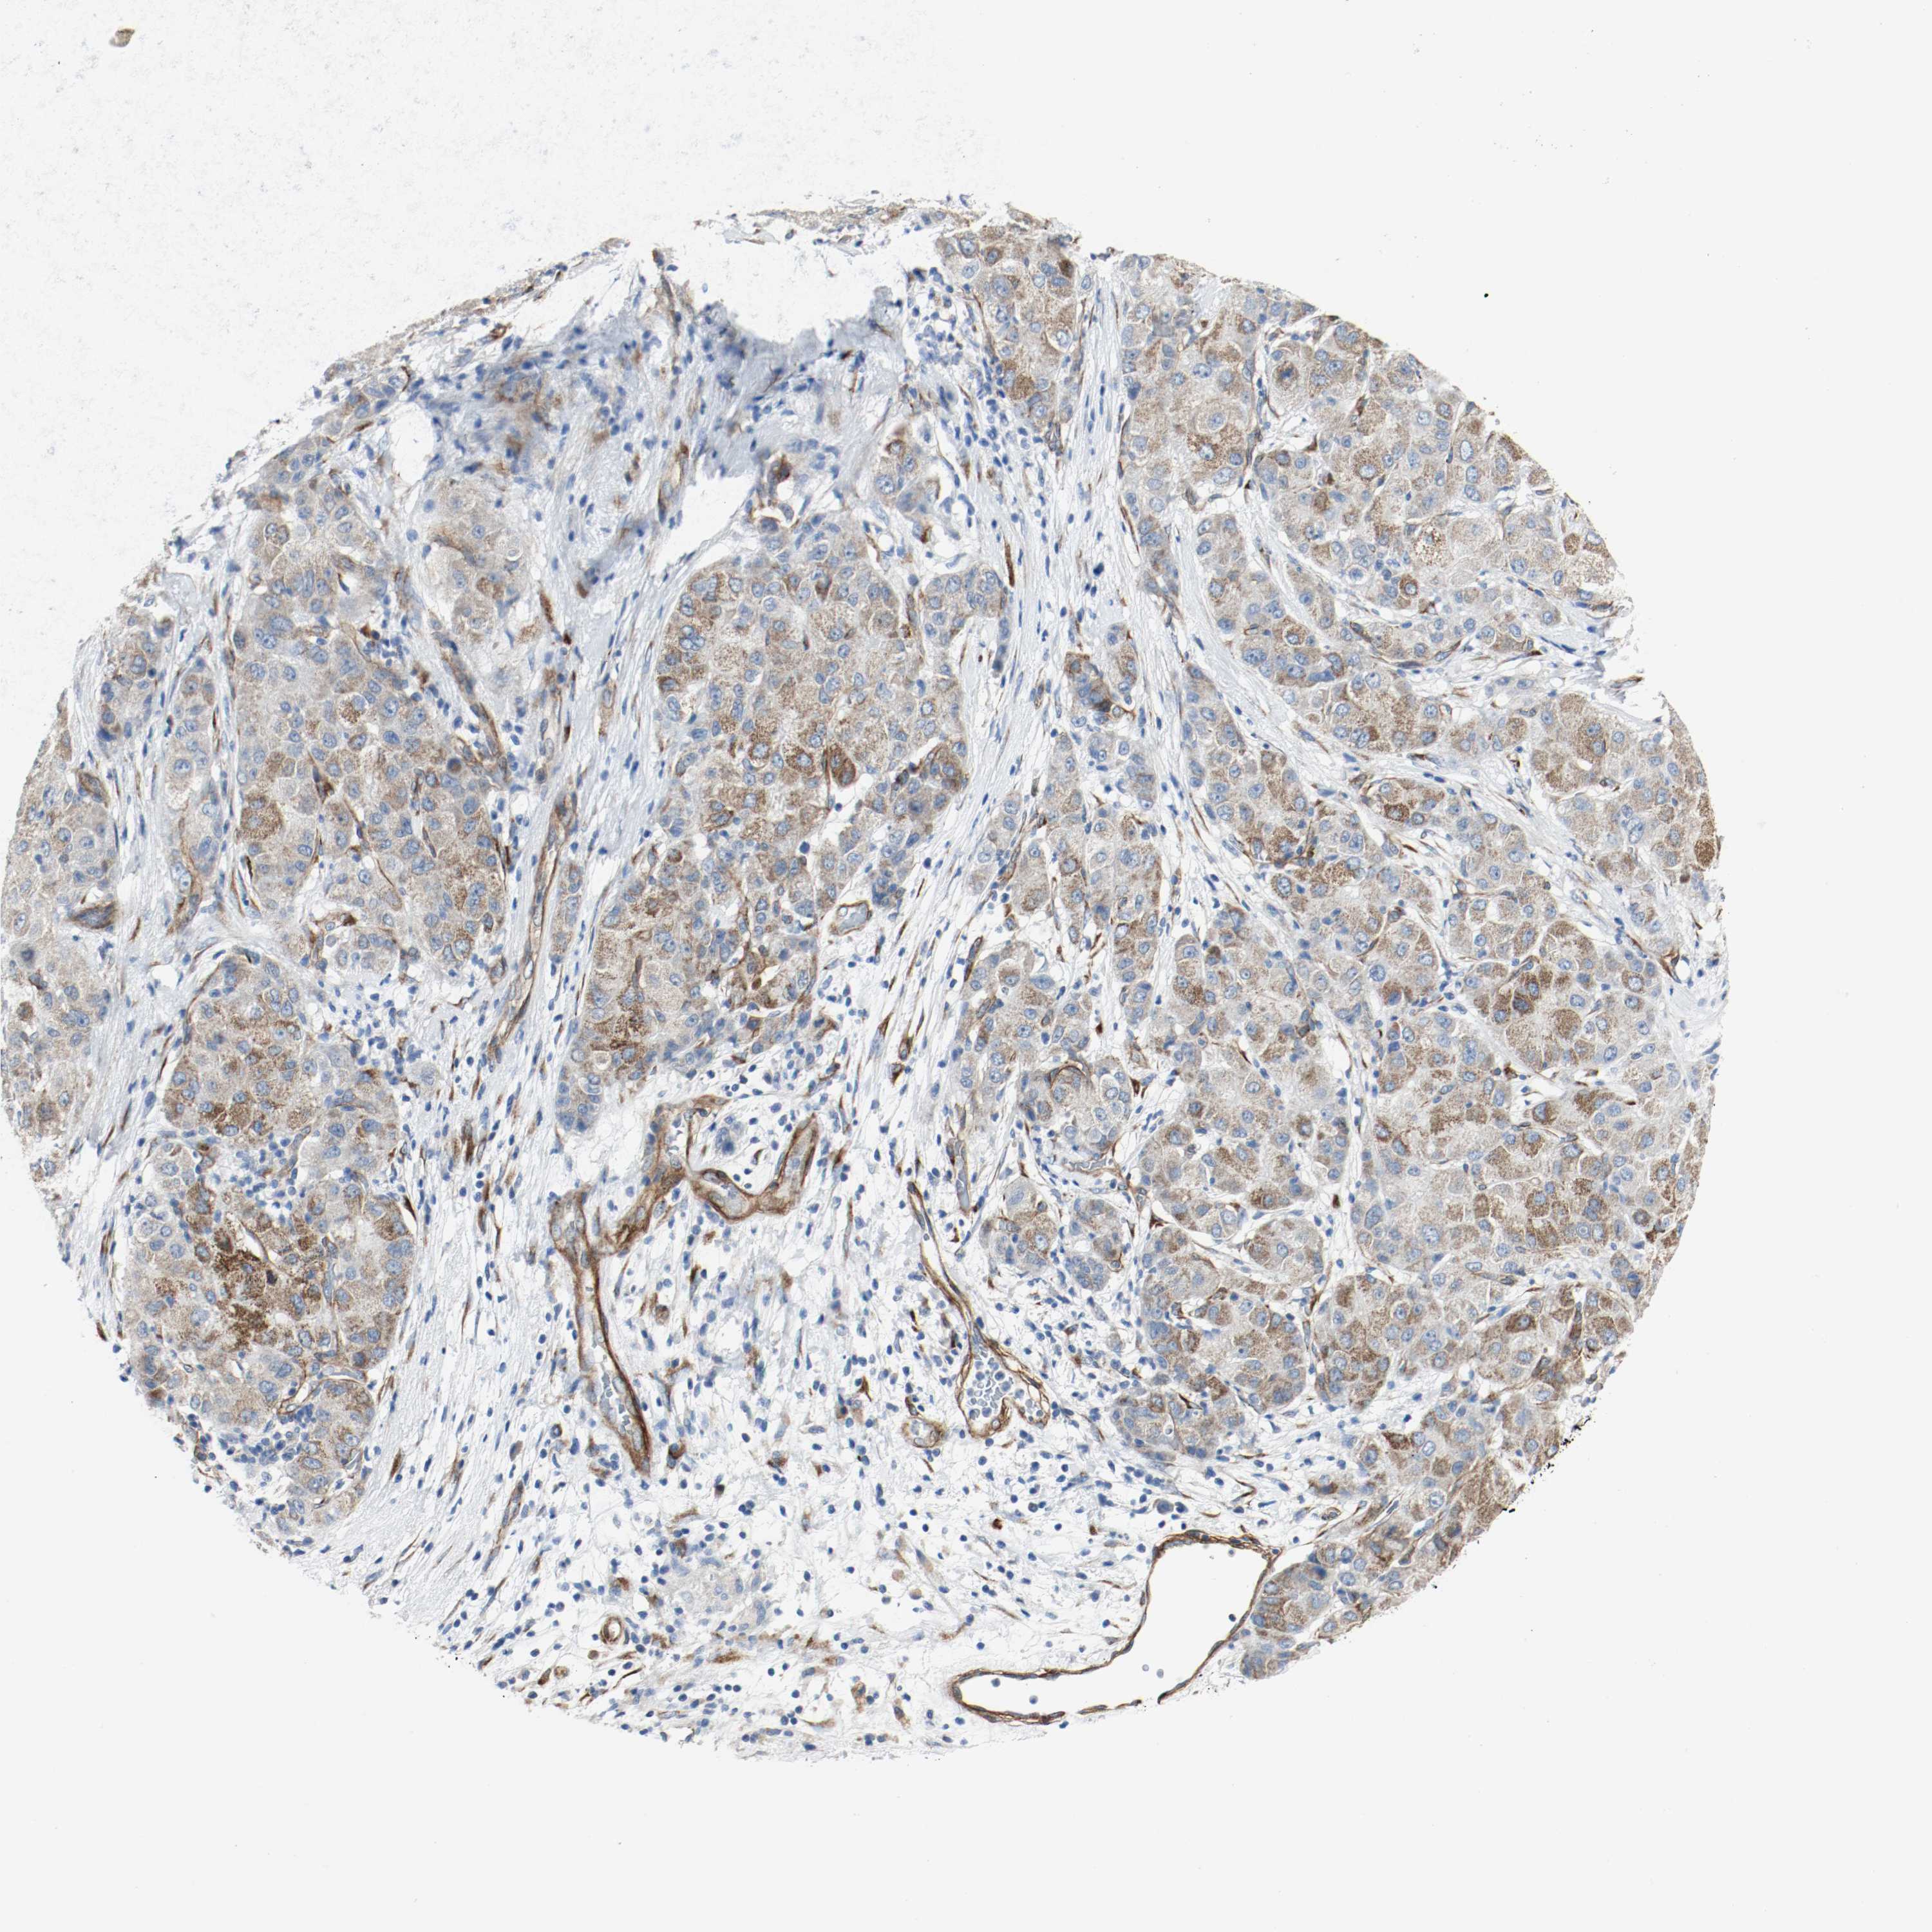

LIVER CANCER - Protein expressioni

A mouse-over function shows sample information and annotation data. Click on an image to view it in a full screen mode. Samples can be filtered based on level of antibody staining by selecting one or several of the following categories: high, medium, low and not detected. The assay and annotation is described here.

Note that samples used for immunohistochemistry by the Human Protein Atlas do not correspond to samples in the TCGA dataset.

Antibody stainingi

Antibody staining in the annotated cell types in the current human tissue is reported as not detected, low, medium, or high, based on conventional immunohistochemistry profiling in selected tissues. This score is based on the combination of the staining intensity and fraction of stained cells.

Each image is clickable and will lead to virtual microscopy that enables deeper exploration of all samples and also displays staining intensity scores, fraction scores and subcellular localization as well as patient and tissue information for each sample.

Antibody HPA004056

Antibody HPA004132

Antibody CAB004256

Staining

High

Medium

Low

Not detected

Intensity

Strong

Moderate

Weak

Negative

Quantity

>75%

75%-25%

<25%

None

Location

Nuclear

Cytoplasmic/membranous

Cytoplasmic/membranous,nuclear

Cholangiocarcinoma

Carcinoma, Hepatocellular, NOS